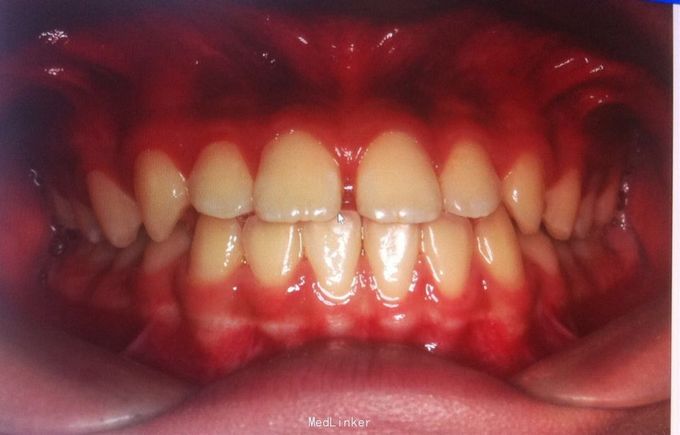

恒牙期 磨牙中性关系 前牙覆合覆盖关系正常 A1B1之间1mm间隙

安氏一类 不拔牙矫治,直丝弓矫治器,排齐整平上下牙列,关闭前牙散在间隙,矫治后磨牙中性关系,前牙正常覆合覆盖,维持现有面型